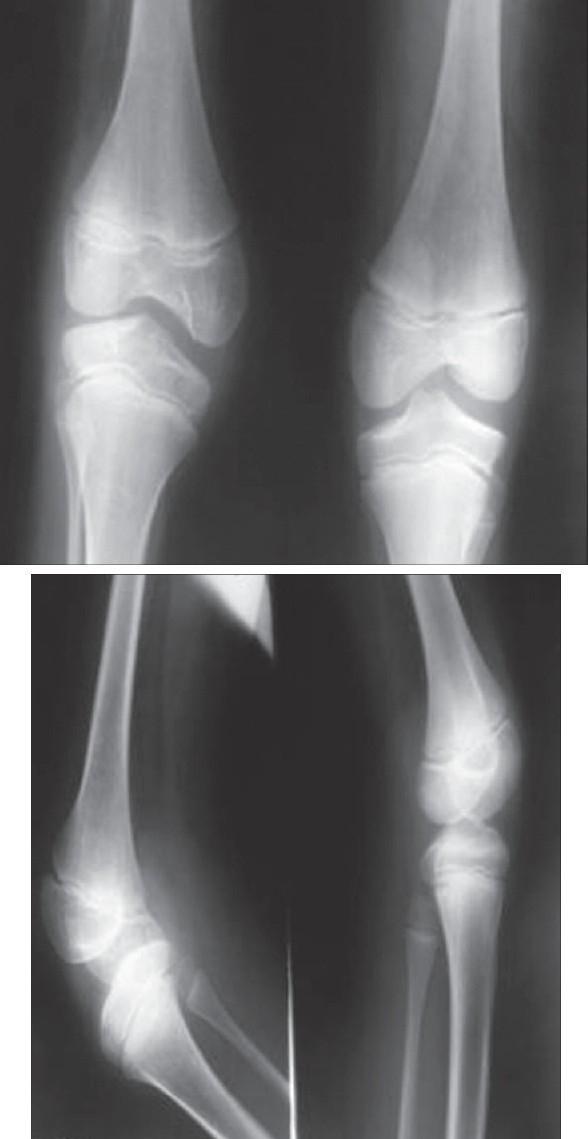

Bilateral congenital absence of patella.

Absence of patella as an isolated anomaly is extremely rare. It is usually absent as part of a syndrome, most commonly hereditary arthro-onchyo-dysplasia (Nail Patella Syndrome). We present a case of congenital bilateral absence of patella in a nine-year-old boy with no associated anomalies.